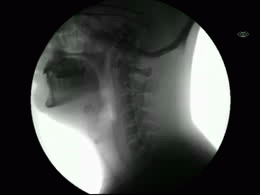

TDN > Actualité Le corps humain aux rayons X … en GIFs animés ! Publié par Elsa Fanjul le 11 Jan 2014 à 10:08 Suivez nous sur Google News Partagez cet article En bonus, découvrez le Giphoscope, ou comment faire des GIFs dans la vraie vie ! Veuillez laisser ce champ videRejoignez nos 875 726 abonnés en recevant notre newsletter gratuite N'oubliez pas de cliquer sur l'email de validation pour confirmer votre adresse email. Si vous ne l'avez pas recu vérifiez dans vos spams. Dernière étape pour confirmer votre inscription : il faut cliquer l'email de confirmation. Vérifiez dans vos spams si vous ne l'avez pas reçu ! A bientôt ! Page précédente Laissez un commentaire Votre adresse e-mail ne sera pas publiée. Les champs obligatoires sont indiqués avec * Votre commentaire * Votre pseudo * Votre adresse e-mail * Cliquez ici pour commenter